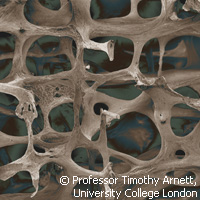

Findings from EU-funded research into the mechanisms behind the beneficial effects of exercise on bones could lead to new treatments for osteoporosis sufferers. The research was carried out as part of the ATPBone ('Fighting osteoporosis by blocking nucleotides: purinergic signalling in bone formation and homeostasis') project, which received nearly EUR 3 million of funding under the 'Health' Theme of the European Commission's Seventh Framework Programme (FP7). The largest European bone biology and osteoporosis research project ever carried out within its field, ATPBone ran from 2008 to 2010 and brought together scientists from Belgium, Denmark, Italy, the Netherlands and the United Kingdom. The pan-European team of scientists investigated how bone tissue is maintained and how specific biochemical signal molecules regulate the degradation of bone as well as the formation of new bone. 'It is well-established that exercise prevents osteoporosis - after the ATPBone project we also know why,' says Professor Peter Schwarz from the Copenhagen University Hospital Glostrup in Denmark, the coordinating institution. For patients, the onset of osteoporosis is characterised by excessive bone loss and frequent bone fractures. Researchers estimate that in 2000, 3.8 million osteoporotic fractures occurred in Europe. Aside from bone fractures, osteoporosis can also be diagnosed by measuring the mineral content in bones by performing a 'dual energy absorptiometry' scan. This can determine whether the patient has the condition or suffers from low bone mass that could develop into osteoporosis later in life. Although treatment can restore some of the lost bone mass, osteoporosis is largely an incurable condition, and is more common in women than men. One in five elderly people with a hip fracture die within a year of developing the fracture. The ATPBone project scientists were able to demonstrate that physical activity and other stimuli to the bones induce the release of the biochemical compound ATP. This biochemical compound regulates bone turnover through action on the so-called purinergic receptors, which have been shown to be present on bone cells. In addition to this finding, the scientists discovered that treating bone cells with parathyroid hormone, which is produced in the human body and is also used by doctors for treatment of severe osteoporosis, induces an increased release of ATP upon mechanical stimulation and that ATP and parathyroid hormone interact on the receptors. This means that the locally acting purinergic signalling system could interact with hormone systems in the body. Niklas Rye Jørgensen, coordinator of the ATPBone project and researcher from Glostrup Hospital and Copenhagen University says: 'Through ATPBone we have shown that the purinergic signalling system has profound effects on bone turnover and that it is a potent system through which we can potentially prevent or even treat osteoporosis.' Jørgensen also outlines that as well as being music to patients' ears, their findings have crucial economic implications for society. In terms of the strain on European health services, direct medical costs related to osteoporotic fractures are estimated to be in the region of EUR 36 billion a year, so any new treatments would help reduce this financial burden. Ultimately, the scientists hope their findings will help meet Europe's requirements for the development of new anti-osteoporotic drugs, and with incidences of osteoporosis only expected to rise further over the coming decades amid an ageing European population, this need has never been greater.For more information, please visit:ATPBONE:http://www.atpbone.org/Copenhagen University Hospital Glostrup:http://www.glostruphospital.dk/menu/